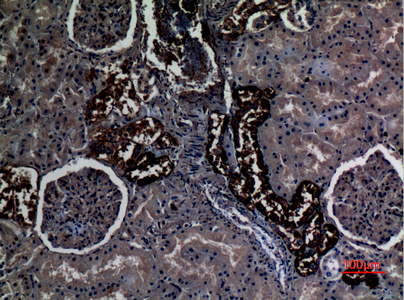

Expressed in brain, testis, placenta, pancreas, esophagus and prostate. Expressed in squamous epithelial tissues (at protein level). According to PubMed:11062476, specifically expressed in kidney.

PMID: 10852913 by Liu Z., et al. Characterization of human RhCG and mouse Rhcg as novel nonerythroid Rh glycoprotein homologues predominantly expressed in kidney and testis.